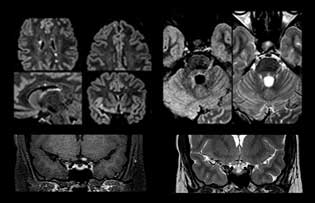

When multiple sclerosis (MS) is suspected, clinicians need a diagnosis early on, so treatment can begin as soon as possible. “A challenge for imaging is that MS lesions in the brain and spine may be very small,” says Dr. Savatovsky. “We need precise imaging to tell exactly where the lesion is, so we need high quality, very high resolution images, preferably in 3D[1]. We need to know if a high T2 signal intensity is suggestive of MS or just aspecific. And we want to visualize active lesions very well.”

“Ingenia 3.0T provides us very good image quality with high SNR, even if we push the resolution. For example, in FLAIR images we may have an isotropic resolution of 0.9 mm. Ingenia allows us to use 3D T1 TSE with BrainView, which has a better sensitivity than 2D spin echo imaging[2] and 3D gradient echo imaging. Ingenia also provides highly reproducible exams, which is important in MS imaging so that follow-up exams at different time points are done the same way.”

For MS imaging in the brain, Dr. Savatovsky uses 3D FLAIR as the basic sequence to visualize the lesions and assess the situation and lesion load. “We count the lesions in each location to determine if the criteria of the disease are fulfilled. We use a T2-weighted sequence because our neurologists are used to it. We compare the lesion load on FLAIR with a 3D T1 post-contrast sequence to help us determine whether lesions are old or new. We typically administer the contrast before the patient enters the machine because it shortens the examination time and allows to visualize active lesions that tend to be more visible after several minutes. When a differential diagnosis is difficult, we add sequences such as susceptibility imaging, because some focal MS lesions have a small vein in the center[3].”

“For MS imaging in the spine, the basic examination includes a sagittal T2 and a post-contrast sagittal T1-weighted sequence in the whole spine. These are done in two stacks and using thin slices, for example 2 mm, without gap. As in the brain, the T2-weighted sequence visualizes the overall lesion load and helps determine if lesions are old or new. The post-contrast T1- weighted sequence helps in assessing if a lesion is new. We will sometimes add a T1 inversion recovery sequence, which has very good sensitivity, if we don’t find any lesions on T2,” Dr. Savatovsky says. “Additionally, if there is contrast enhancement outside the spine, it’s usually not MS but another kind of inflammation.”